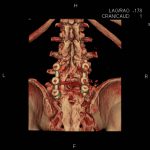

În cazul traumatismelor cranio-cerebrale:

- Evaluarea deplasării liniei mediane

- Evaluarea cisternelor perimezencefalice

- Diagnosticul edemului cerebral, a contuziei cerebrale, a leziunilor axonale difuze edematoase/hemoragice, a dilacerării cerebrale, a hematomului intraparenchimatos posttraumatic, a hematoamelor subdurale/extradurale (acute, subacute, cronice), a hemoragiei intraventriculare, a hemoragiei subarahnoidiene

- Diagnosticul traumatismelor de bază de craniu